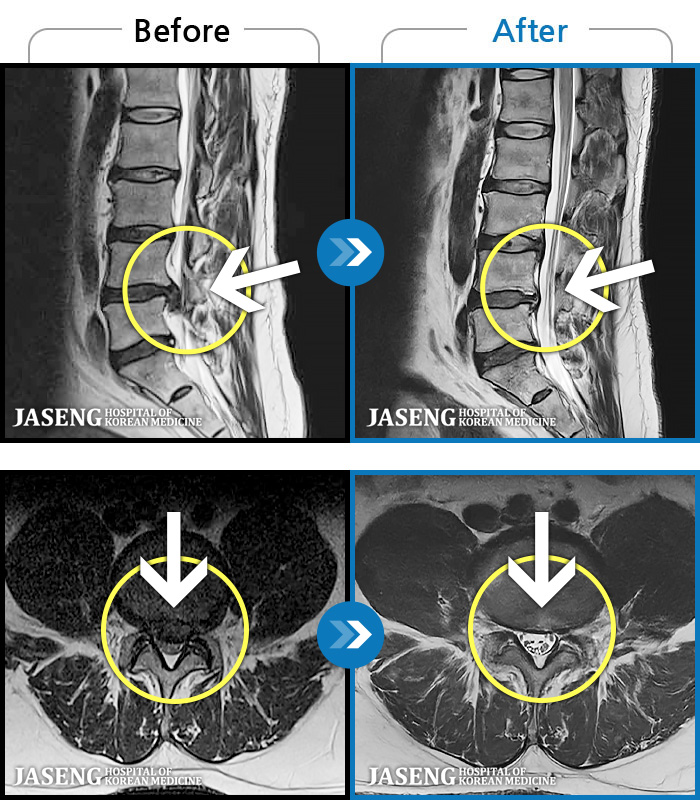

MRI ġ

119 MRI ũ ʸ Ȯϼ.

[Կñ:22.08.30~24.08.05]

[_㸮ũ] ٸ ߳ .

No.118

ȸ 506

2024.12.24